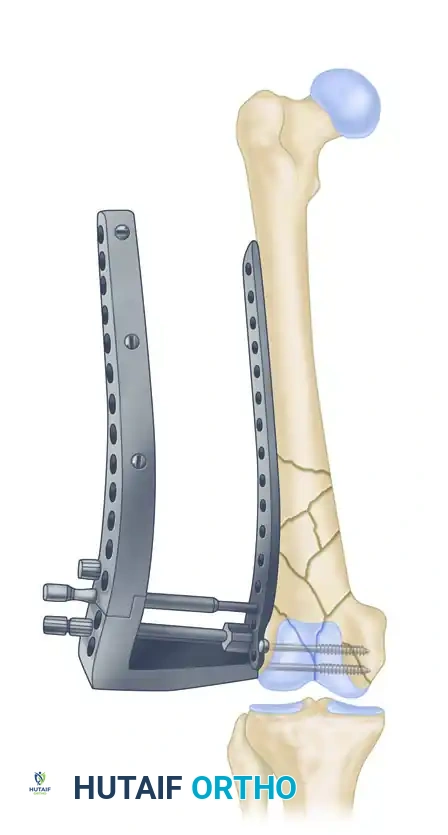

Less invasive stabilization technique (LISS) plate. Letters are used to identify distal plate holes; numbers are used to identify diaphyseal plate holes.

Proper positioning of the lateral plate is paramount. The insertion guide must be aligned correctly with the femoral shaft to prevent malreduction.

The insertion guide has a tendency to tilt toward the floor. When positioned properly on the lateral condyle, the insertion guide is internally rotated approximately 10 degrees relative to the femoral shaft. Plate position is adjusted if necessary.

A Kirschner wire is inserted through the stabilization bolt to provisionally hold the plate to the distal condylar block.